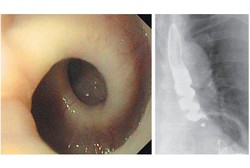

Setelah berat badannya turun, seorang wanita Swiss berusia 87 tahun mengaku mengalami kram hebat di dadanya. Mungkin terdengar biasa, tapi ternyata kram ini disebabkan kerongkongan si nenek memilin dengan sendirinya kapan pun ia menelan makanan.